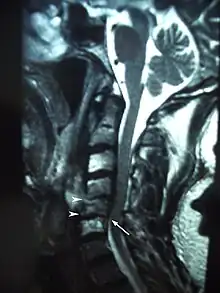

Radiation therapy destroys cancer primarily by causing DNA damage that promotes cell death.[4][5] Tumor cells within a cancer are especially susceptible to damage by radiation as they frequently develop mutations in the DNA repair mechanisms that allow normal, healthy cells to recover from radiation damage.[12] However, excessive radiation doses can cause even normal cells to be overwhelmed by DNA damage and lead to local tissue changes and necrosis. Scientists have been conducting investigations into the exact mechanisms of these changes to help create treatments since osteoradionecrosis (ORN) was first described by Regaud in 1922.[13] Several competing theories have emerged over the years with resultant changes to accepted treatments. Initially, it was believed that ORN arose from a combination of radiation, trauma and infection.[14] According to this belief, radiation damage to the bone caused the bone to weaken, making it susceptible to microfractures caused by trauma and allowing bacteria to invade.[14] This theory placed ORN on a spectrum of disease with osteomyelitis, so it was primarily treated with antibiotics.[3] In 1983, Robert E. Marx, a prominent oral and maxillofacial surgeon, refuted the notion that trauma and infection were requirements in the development of ORN.[3] Marx proposed that ORN was the result of cumulative tissue damage caused by radiation, creating disturbances in cell metabolism and homeostasis that resulted in cell death and hypocellular tissues.[15] In addition, radiation causes injury to the endothelial cells of local vasculature, creating a hypovascular environment which leads to decreased oxygen delivery resulting in hypoxic tissues.[15] The decrease of vasculature helps explain why the mandible is more commonly affected than maxilla, as the mandible is served primarily by the inferior alveolar artery, whereas the maxilla is served by various arteries and has a more robust blood supply.[16] In sum, Marx believed that ORN was essentially hypocellular-hypovascular-hypoxic tissues behaved much like chronic non-healing wounds.[3][15] Initial reports by Marx and others showing that treatment with hyperbaric oxygen (HBO) prevented ORN helped support this theory.[17] However, later studies began to raise doubts about the effectiveness of HBO therapy and question whether Marx's theory was comprehensive enough to guide treatment.[18]

Current understanding is guided primarily by the work of Delanian and Lefaix, who proposed the radiation-induced fibroatrophic (RIF) process.[19] Advances in lab techniques allowed scientists to perform more detailed studies of ORN specimens. Analysis of samples showed that tissues undergoing ORN underwent three phases of disease: 1) prefibrotic, 2) constitutive organized and 3) late fibroatrophic phases.[19] During the prefibrotic phase, injury to endothelial cells secondary to radiation causes destruction of local vasculature, and recruitment of inflammatory cells and fibroblasts via pro-inflammatory cytokines like TNF-α, FGF-β and TGF-β1.[19] In addition, osteoblasts within the bone are damaged and destroyed, leading to decreased production of normal bone tissue.[3] In the constitutive organized phase, fibroblasts persist and are converted to myofibroblasts by these same cytokines, that begin to fibrous extracellular matrix (ECM) within the affected bone.[19] Consequently, the increased production of ECM by myofibroblasts coupled with decreased production of osteoid by osteoblasts results in weakened bony tissue.[19] Finally, during the late fibroatrophic phase, the affected bone becomes hypocellular as myofibroblasts begin to die and leave behind weak, fibrotic tissue.[19] Ultimately, these tissues are fragile and susceptible to damage by trauma or infection with little ability to repair or defend themselves due to the lack of vasculature caused during the pre-fibrotic phase.[19] Given this understanding of the pathophysiology of ORN, current treatments are targeted at decreasing inflammatory cytokines and reducing free radical damage to DNA.[19][20]